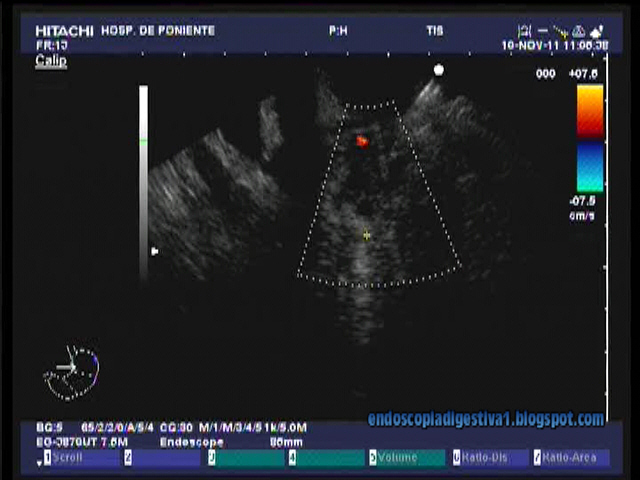

Paciente de 74 años con antecedentes de HTA, DM tipo II, FA en tratamiento con acenocumarol, obesidad y EPOC. Fumador de > 20 c/día y bebedor de hasta100 gr de etanol/día. En agosto de 2011 ingresa por un cuadro de colangitis aguda, destacando analíticamente una ligera hipertransaminemia (GOT 197 UI/L, GPT 173 UI/L, BRT 4 mgr/dl con predominio de la fracción directa. Los marcadores tumorales (CEA y Ca 19.9 eran normales). En las pruebas de imagen realizadas destaca una dilatación de la vía biliar extrahepatica hasta la cabeza pancreática (13 mm) sin claros defectos de replección en su interior, dilatación discreta de la vía biliar intrahepática en la ecografía, sin colelitiasis. En el TAC realizado se aprecia además de lo referido, un desflecamiento y aumento de tamaño de la cabeza pancreática, sin organizarse una masa como tal. No pudo practicarse CPRM por la obesidad del paciente. Se intentó CPRE que resultó infructuosa debido al hallazgo de una estenosis de «dudoso aspecto» en la primera rodilla duodenal que impedía el paso del duodenoscopio. Las biopsias tomadas de la lesión demostraron únicamente el hallazgo de tejido inflamatorio crónico sin la presencia de células neoplásicas. Por un motivo similar no se pudo realizar una USE-PAAF en otro centro. El paciente respondió bien al tratamiento antibiótico y fue dado de alta, pendiente de revaloración precoz y sesión conjunta con cirugía. A los 2 meses el paciente reingresa por un nuevo cuadro de colangitis. Clínicamente se encontraba bien, sin dolor, aunque había perdido en el últino año unos 10 kgr de peso. Persistía una colestasis disociada. Se realizó una CPRM, donde aparecía una lesión en la cabeza pancreática mal definida (intesidad intermedia en T2 e intensidad baja en T1) de unos 2 x 2 cm, en íntimo contacto con la pared duodenal que está engrosada. La lesión es de aspecto fibrótico y por ello compatible con un proceso inflamatorio crónico en primer lugar, auqnue no puede descartarse una neoformación. Se aconseja USE-PAAF. Se realiza una EDA con un gastroscopio de fino calibre (8 mm), que demuestra la estenosis descrita en la primera rodilla duodenal, extendiendose a la 2ª, pero franquebale. Las biopsias que se tomaron resultaron negativas para neoplasia (proceso inflamatorio crónico). Se prevé viable una USE-PAAF en el apex bular que se realiza, apreciando una masa mal definida, heterogenea que contacta intimamente con la pared duodenla, de unos 2 x 2.5 cm en la cabeza pancreática. La PAAF no evidencia celulas neoplásicas, aunque si de tipo inflamatorio crónico. Actualmente nos inclinamos por le diagnóstico de pancreatitis crónica con masa inflamatoria en la cabeza que estenosa ligeramente la luz duodenal y el colédoco, provocando colangitis de repetición. Dentro de las dos posibilidades terapeúticas (endoscópica o quirúrgica) y tras hablar con el paciente, se va a intentar dilatar la estenosis duodenal con la idea de realizar una CPRE y colocar una prótesis biliar metálica recubierta que evite las colangitis de repetición.